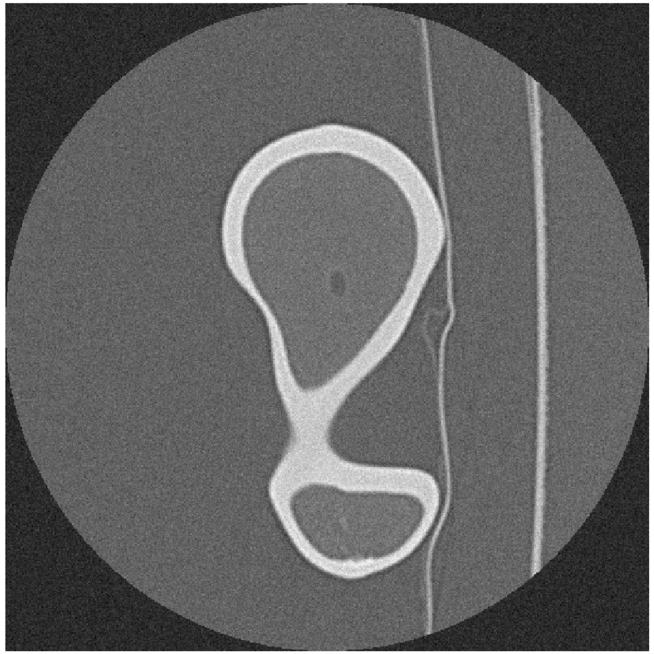

Two outputs may be produced after segmentation refinement (Fig. 2), a high-resolution point cloud model obtained directly from the interpolated image, and a down-scaled version of the high-resolution segmentation. The surface mesh model obtained from the point cloud will be referred as Point Cloud (PC) model. Since image refinement is performed independently in each image, the PC model is produce directly from a set of equally spaced contours by tiling the cloud points. The surface mesh of the down-scaled version was generated in Simpleware ScanIPTM v4.0𝑣4.0v4.0, with standard pre-smoothing and mesh refinement settings [49][50], and will be referred simply as ScanIP Mesh (SM) model. The segmentation pipeline was tested in noise-free and noisy images, corrupted with AWGN with a standard deviation of σNoise=10subscript𝜎𝑁𝑜𝑖𝑠𝑒10\sigma_{Noise}=10 HU. Fig. 5 shows the sub-stpng of the segmentation refinement process when applied to both noise-free and noisy images. The Hausdorff Distance (HD) and the Mean Symmetric Distance (MSD) [51] were applied to evaluate each segmentation outcome.

Figure 5: Segmentation refinement pipeline applied to the Dataset #1: in (a) the original image data without noise; in (b) the image data after de-noising with anisotropic diffusion and image deconvolution; in (c) image cropping and interpolation around the pre-segmented region; and in panel (d) the final segmentation contour superimposed over the pre-segmentation mask; in (e), (f), (g) and (h) image refinement is applied to the same image corrupted with AWGN

Fig. 6 shows the final PC model obtained from the segmentation of Dataset #1 and the comparison with the Nikon Metris LK𝐿𝐾LK V20𝑉20V20 gold standard, whereas Fig. 7 depicts the down-scaled segmentation within Simpleware ScanIPTM v4.0𝑣4.0v4.0 overlapped with reference surface. A close agreement between both PC and SM, and the gold standard is observed for both models. The agreement between the PC and SM model and the gold standard for all noise-free and noisy Datasets regarding the distance measures are summarized in Table II and Table III, respectively.

Figure 7: On left (a) the domain pre-segmentation and final segmentation after refinement for the Dataset #1, in the middle (b) the surface mesh generated with Simpleware ScanIPTM and the reference model, and the comparison between the two models (c)